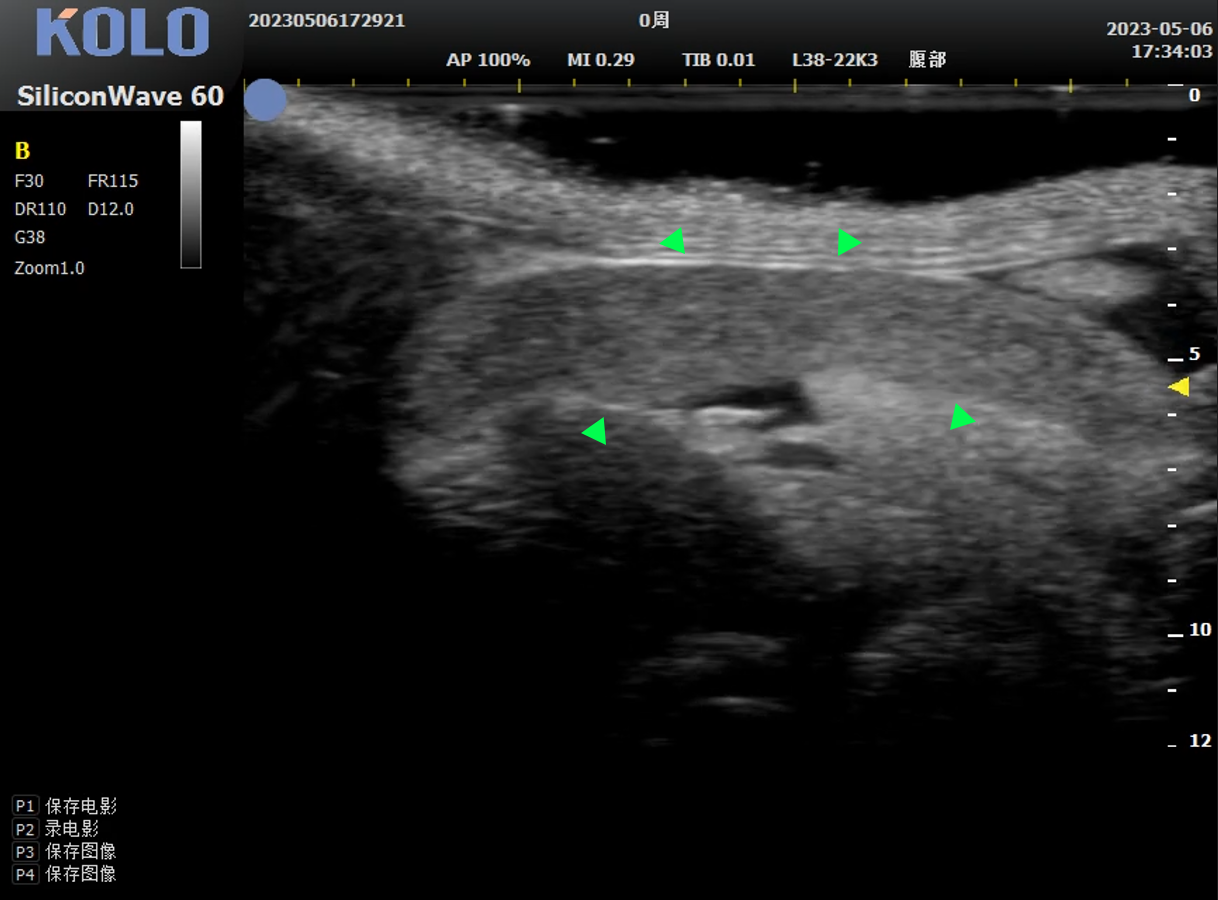

可以检测血管的切面影像,显示病变区域的血管解剖结构、血流方向、血流速度和血流状态的改变,可利用血流明暗探查判断管腔狭窄,精确测量实验动物的血管管壁。

可应用于动脉粥样硬化模型血管壁的形态观察,血流峰值速度测量;动脉瘤的肿瘤位置确定及动脉瘤管径测量等。

小鼠颈动脉